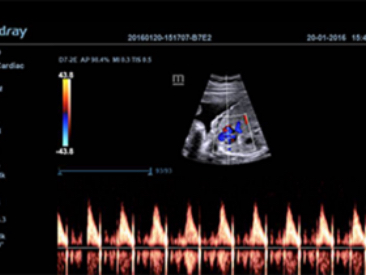

ImĂĄgenes clĂnicas